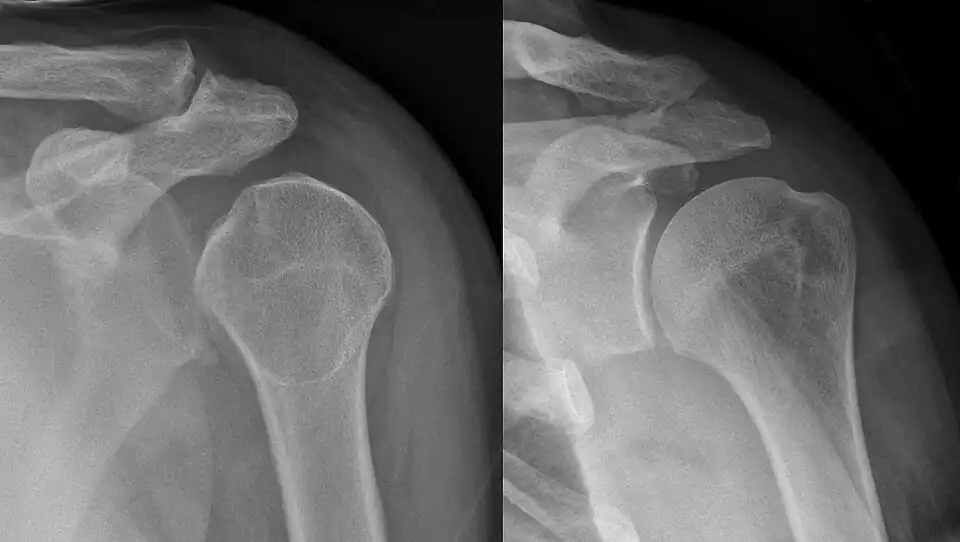

The light bulb sign is a radiological finding observed on plain radiographs in the context of posterior shoulder dislocation.[1] It refers to the abnormal, rounded appearance of the humeral head, which resembles a "light bulb," due to internal rotation of the arm following dislocation.[2]

In posterior shoulder dislocation, the humeral head is displaced posteriorly out of the glenoid cavity. This injury is frequently associated with internal rotation where the humeral head rotates internally, altering its usual elliptical contour to a more rounded shape, creating the "light bulb" appearance. On anteroposterior (AP) radiographs, the humeral head no longer overlaps the glenoid, further emphasizing its abnormal shape.

The light bulb sign is best observed on an AP radiograph of the shoulder.[5] Key features include:

- Rounded humeral head: The humeral head appears symmetrically rounded, resembling a light bulb due to internal rotation.

- Loss of normal glenohumeral overlap: The humeral head is posteriorly displaced, disrupting the alignment with the glenoid cavity.

- Rim sign: Widening of the joint space (>6 mm) between the medial edge of the humeral head and the glenoid. This sign is not specific to posterior dislocation, and can occur also in hemarthrosis.[6]